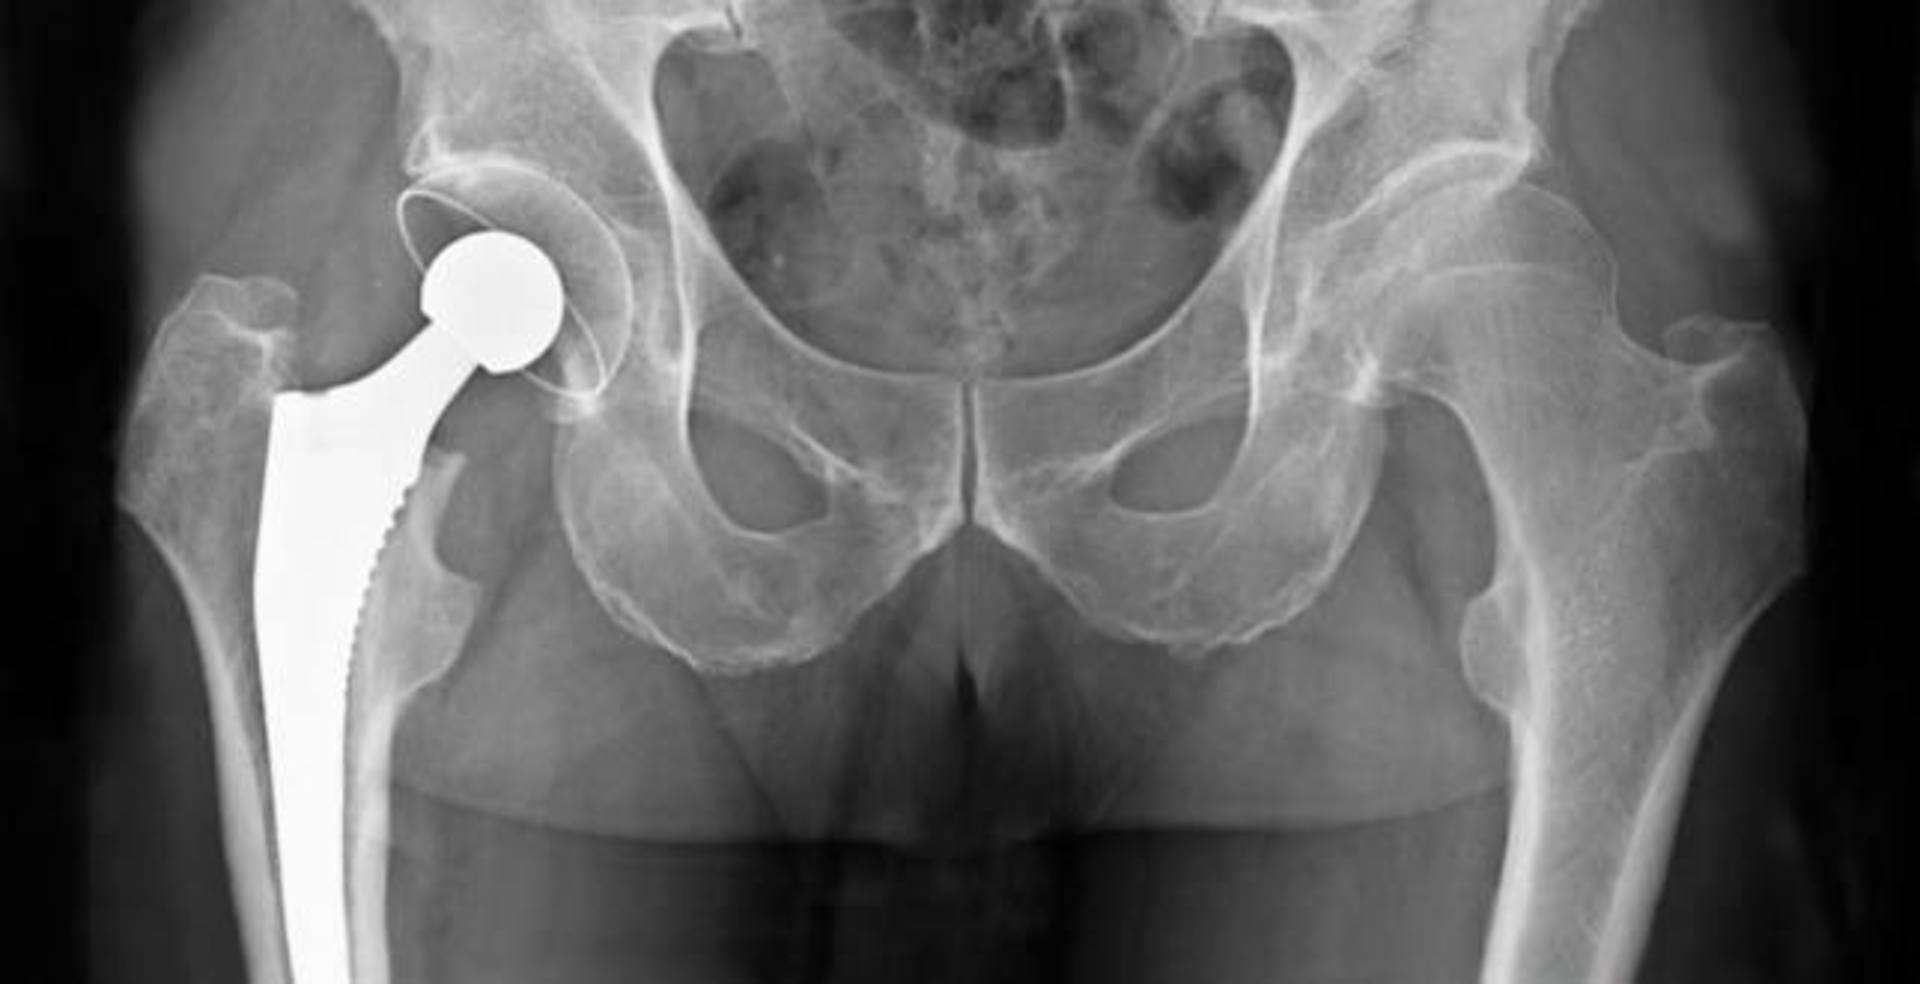

Protesis Total de Cadera

El desgaste de la articulacion de la cadera (coxofemoral) puede generar dolor y causar que las personas no tengan una vida plena. La mejor opsicion para este padecimiento es el recambio de la articulacion.